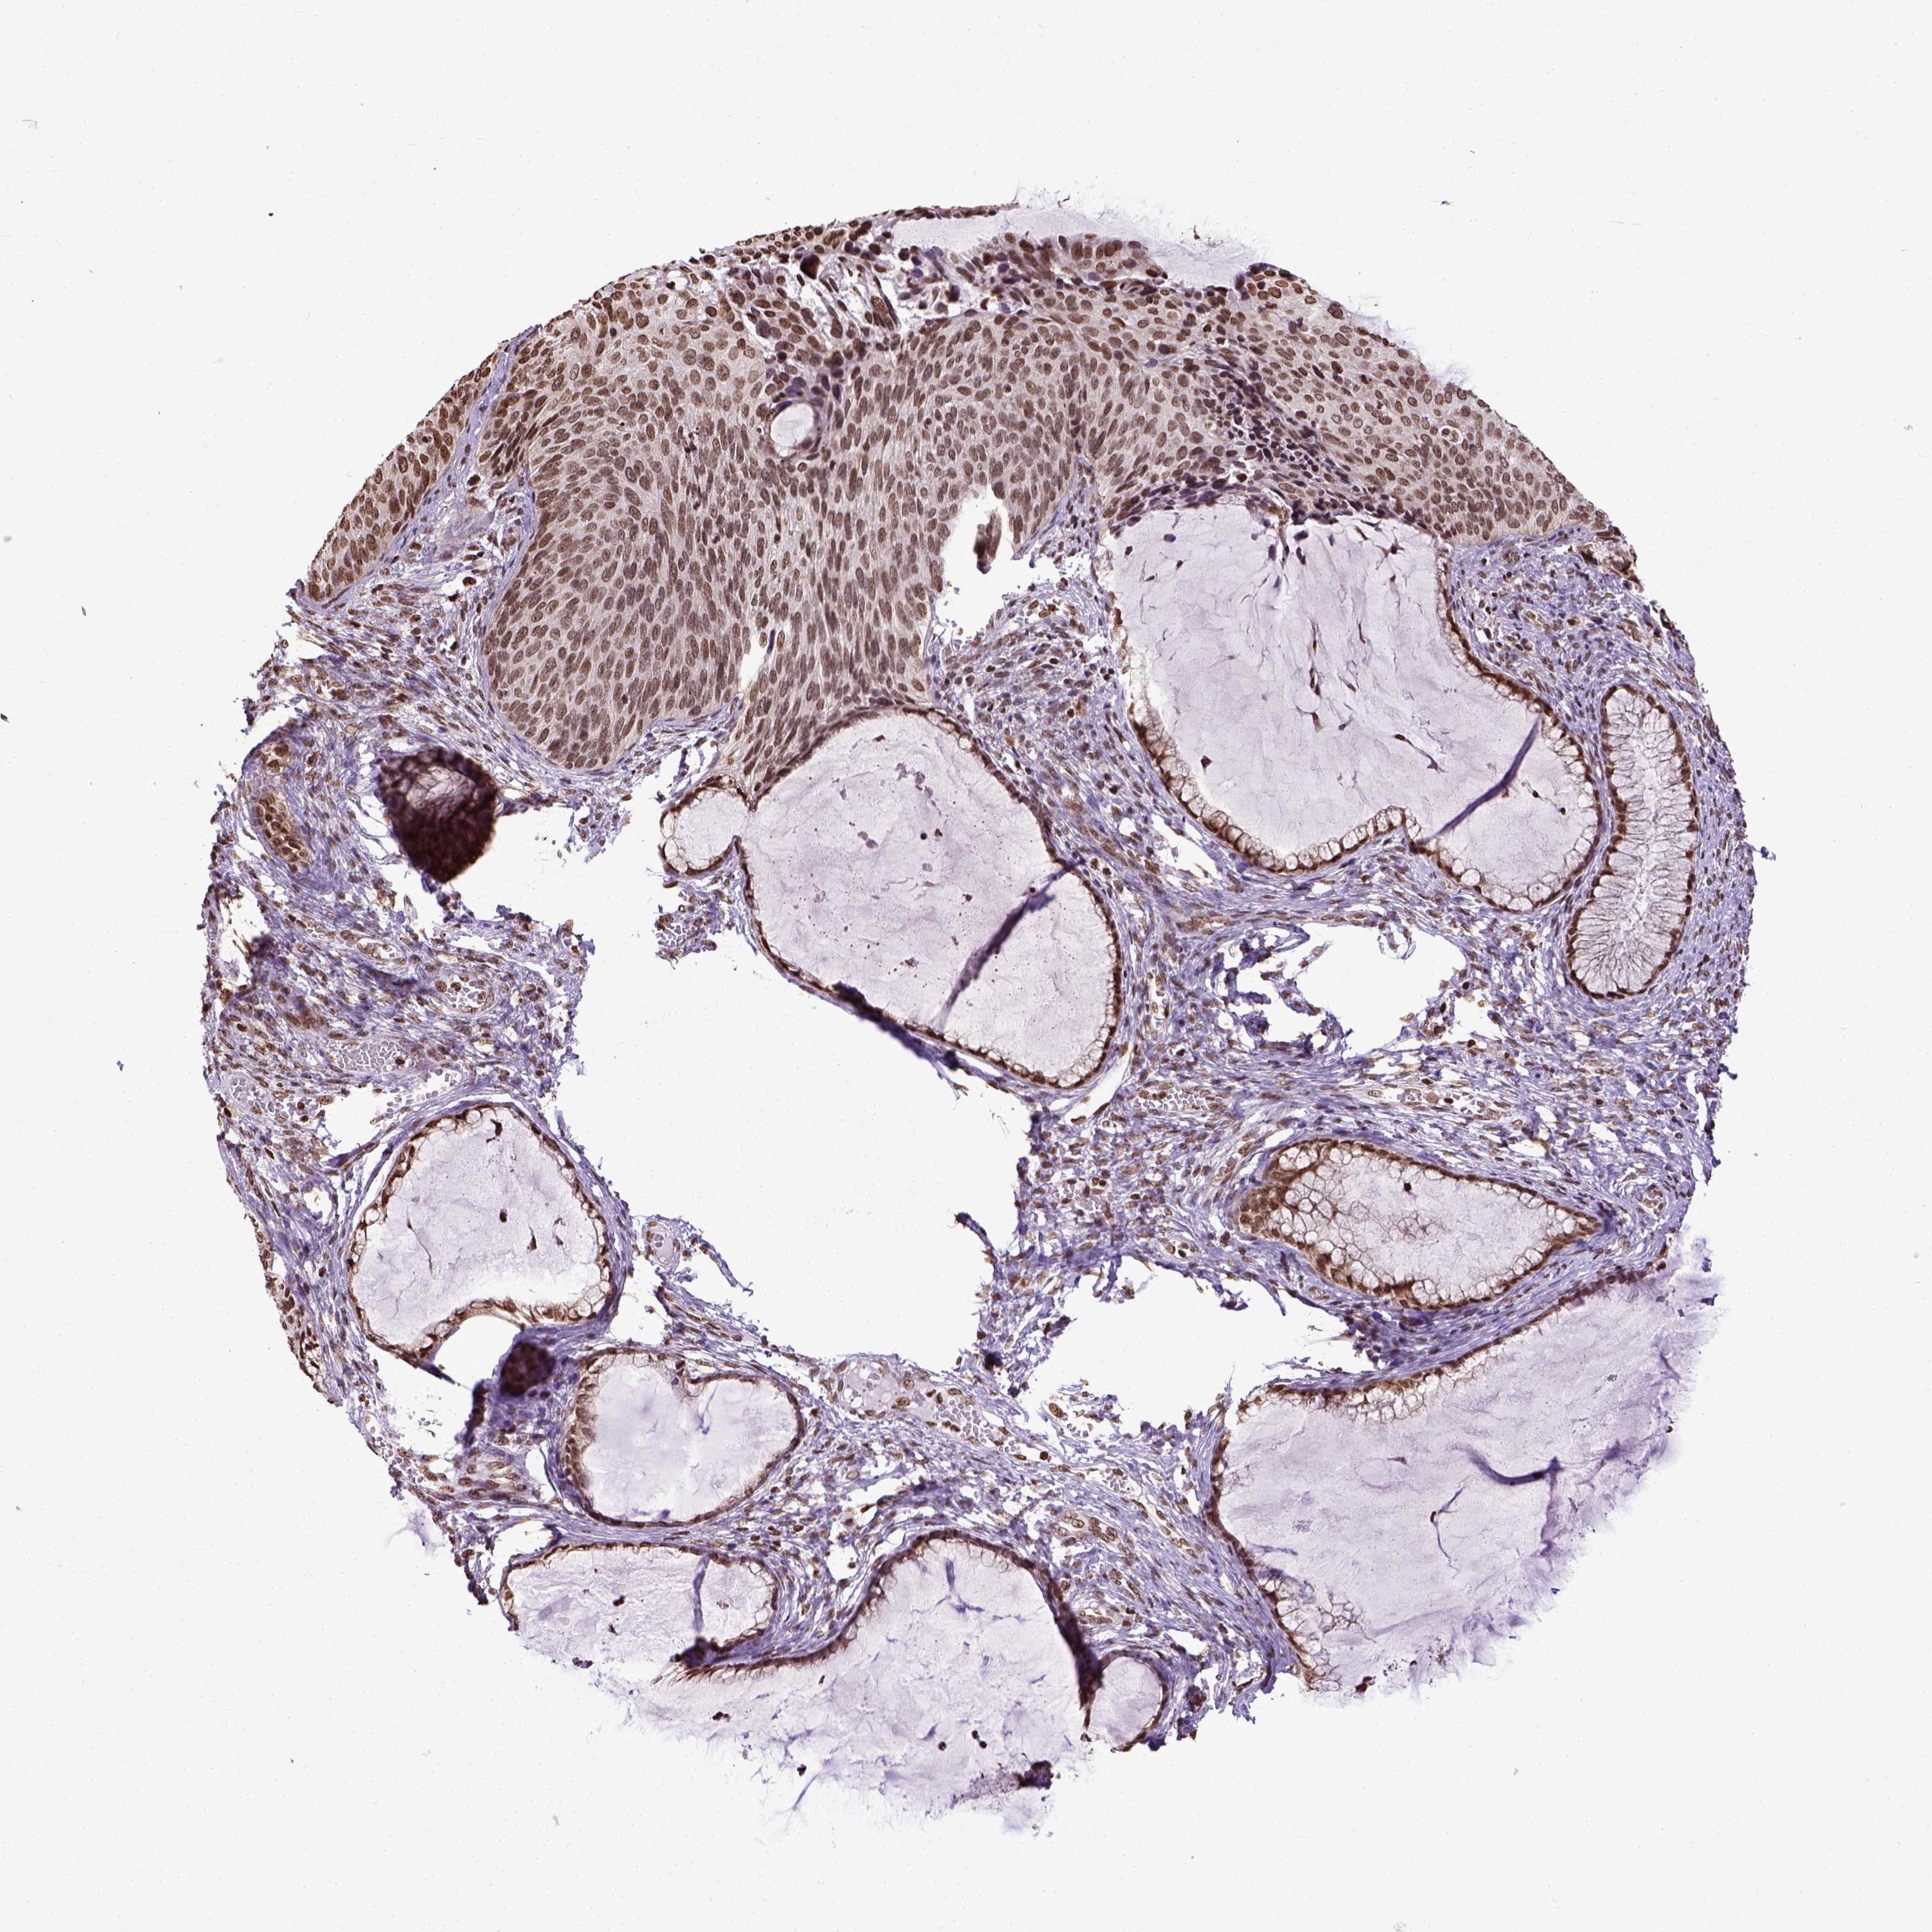

CERVICAL CANCER - Protein expressioni

A mouse-over function shows sample information and annotation data. Click on an image to view it in a full screen mode. Samples can be filtered based on level of antibody staining by selecting one or several of the following categories: high, medium, low and not detected. The assay and annotation is described here.

Note that samples used for immunohistochemistry by the Human Protein Atlas do not correspond to samples in the TCGA dataset.

Antibody stainingi

Antibody staining in the annotated cell types in the current human tissue is reported as not detected, low, medium, or high, based on conventional immunohistochemistry profiling in selected tissues. This score is based on the combination of the staining intensity and fraction of stained cells.

Each image is clickable and will lead to virtual microscopy that enables deeper exploration of all samples and also displays staining intensity scores, fraction scores and subcellular localization as well as patient and tissue information for each sample.

Antibody HPA004705

Staining

High

Medium

Low

Not detected

Intensity

Strong

Moderate

Weak

Negative

Quantity

>75%

75%-25%

<25%

None

Location

Nuclear

Cytoplasmic/membranous

Cytoplasmic/membranous,nuclear

Squamous cell carcinoma, NOS

Adenocarcinoma, NOS